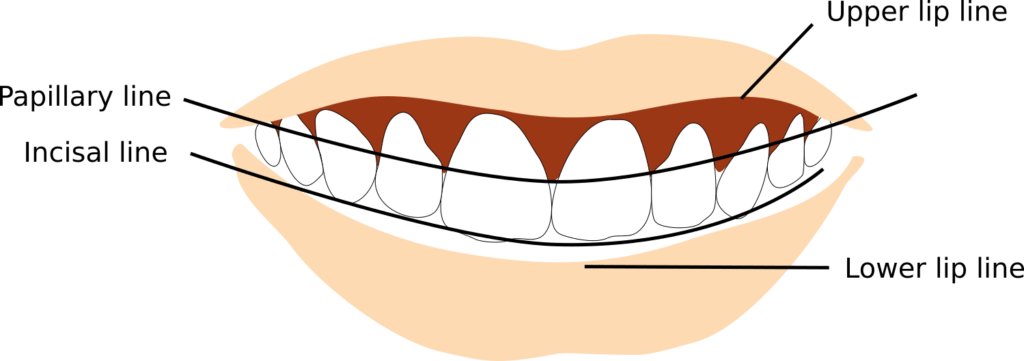

A clinician would note any vertical and left-right asymmetry, knowing that certain proportions are considered to be the most aesthetically pleasing. With the teeth together at rest the lips should passively rest against each other. This is proper lip posture/lip competence. A gap of more than 3 or 4 mm indicates lip incompetence. When the jaw is at rest, there should be 2-4mm of incisor teeth visible beyond lip margin. 1-2mm of gingiva should be visible during a smile, any more is considered a “gummy smile”.